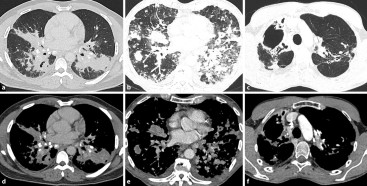

Computertomografie | Moderne Bildgebung des Lungenhilus | springermedizin.de